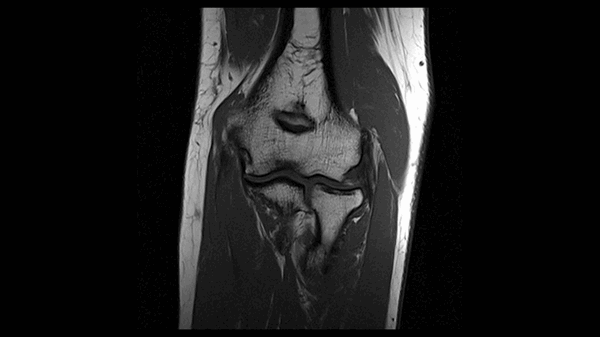

На снимке - МРТ локтевого сустава

МР-снимок локтевого сочленения - вариант нормы

Локтевой сустав (МРТ анатомия)

Описание исследования 1 - головка лучевой кости 2 - венечный отросток локтевой кости 3 - локтевая кость 4 - локтевой отросток 5 - сухожилие трехглавой мышцы 6 - медиальная коллатеральная связка локтевого сустава 7 - лучевая коллатеральная связка локтевого сустава 8 - латеральная коллатеральная связка 9 - латеральный надмыщелок плечевой кости 10 - сухожилие двуглавой мышцы плеча 11 - плечевая мышца 12 - длинный лучевой разгибатель запястья 13 - блок плечевой кости 14 - локтевая мышца 15 - глубокий сгибатель пальцев 16 - локтевой сгибатель запястья 17 - трехглавая мышца 18 - кольцевидная связка лучевой кости 19 - двуглавая мышца плеча 20 - супинатор 21 - плечелучевая мышца 22 - круглый пронатор 23 - разгибатель пальцев 24 - лучевой сгибатель запястья 25 - поверхностный сгибатель пальцев 26 - локтевой нерв 27 - локтевой сгибатель запястья 28 - короткий лучевой разгибатель запястья 29 - общее сухожилие разгибателей 30 - общее сухожилие сгибателей и круглого пронатора 31 - бугристость лучевой кости 32 - головка плечевой кости 33 - медиальный надмыщелок плечевой кости 34 - гребень супинатора 35 - трапециевидная связка (lacertus fibrosus) 36 - наружная головка трехглавой мышцы плеча 37 - длинная головка трехглавой мышцы плеча 38 - медиальная головка трехглавой мышцы плеча 39 - общее сухожилие сгибателей